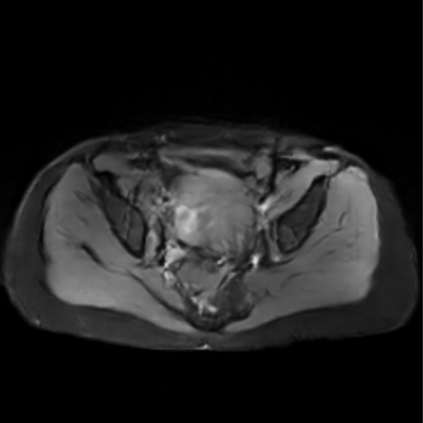

Motion artifacts are a primary source of magnetic resonance (MR) image quality deterioration with strong repercussions on diagnostic performance. Currently, MR motion correction is carried out either prospectively, with the help of motion tracking systems, or retrospectively by mainly utilizing computationally expensive iterative algorithms. In this paper, we utilize a novel adversarial framework, titled MedGAN, for the joint retrospective correction of rigid and non-rigid motion artifacts in different body regions and without the need for a reference image. MedGAN utilizes a unique combination of non-adversarial losses and a novel generator architecture to capture the textures and fine-detailed structures of the desired artifacts-free MR images. Quantitative and qualitative comparisons with other adversarial techniques have illustrated the proposed model's superior performance.

翻译:移动文物是磁共振(MR)图像质量恶化的一个主要来源,对诊断性能产生强烈影响。目前,MR运动的校正要么是预期性的,借助运动跟踪系统,要么是追溯性的,主要是利用成本昂贵的计算迭代算法。在本文中,我们使用名为MedGAN的新颖的对抗性框架,联合追溯性地校正不同身体区域的硬性和非硬性运动文物,而不需要参考图像。 MedGAN利用非对抗性损失和新型生成器结构的独特组合来捕捉无MR图象的纹理和精细详细结构。 与其他对抗性技术的定量和定性比较展示了拟议模型的优异性表现。